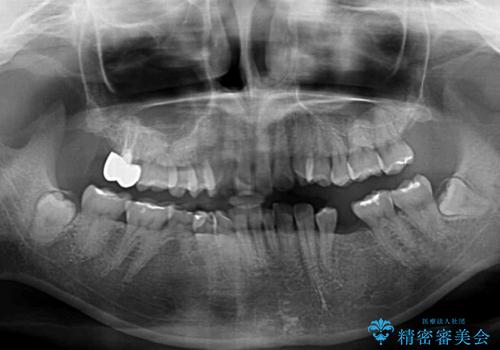

乳歯が抜け落ちた後の後続永久歯が欠損しているため、スペースが残っておりました。

口元の突出感を気にしているのであれば欠損スペースを利用して抜歯矯正を行うことも可能ですが、横顔の印象はスッキリとしている状態であったため、矯正治療でスペースを閉じきることは不可能と判断し、インプラントによる補綴治療を行うこととしました。

第二小臼歯の欠損によるが乳歯残存や欠損が多く、この乳歯は後続永久歯に比べて幅が非常に大きいため、教聖地料によるスペースクローズが難しいことが一般的です。